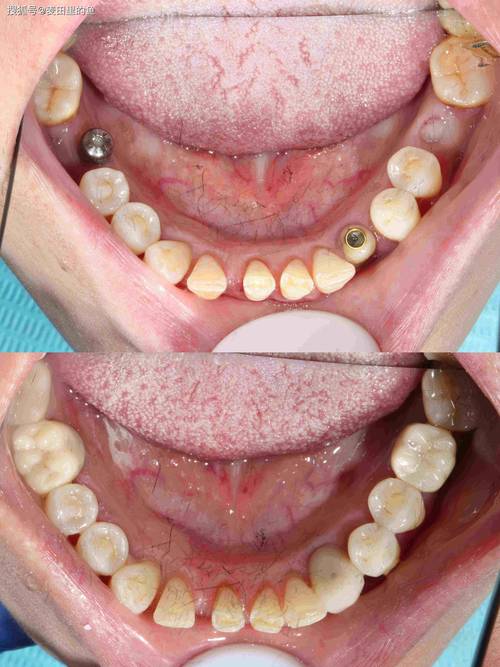

- 二期手术(若为埋植式种植体):对于埋植式种植体(种植体顶部完全埋入牙龈下),需行二期手术切开牙龈,暴露种植体基台连接部位,安装愈合基台,让牙龈形成袖口,2-4周后取模。

- 取模:采用数字化印模(口内扫描仪)或传统印模(用聚醚硅橡胶或聚加硅橡胶取模),获取精确的种植体及周围牙龈形态,送技工室制作牙冠。

- 牙冠制作与戴牙:磨牙区牙冠需承受较大咬合力,材料通常选择全瓷冠(如氧化锆全瓷冠)或金属烤瓷冠,强度高、耐磨性好,技工室制作完成后,医生试戴牙冠,检查边缘密合度、颜色、形态及咬合关系(调整咬合避免早接触、创伤颌),确认无误后用粘接剂固定(种植体基台通常采用粘接固位或螺丝固位)。